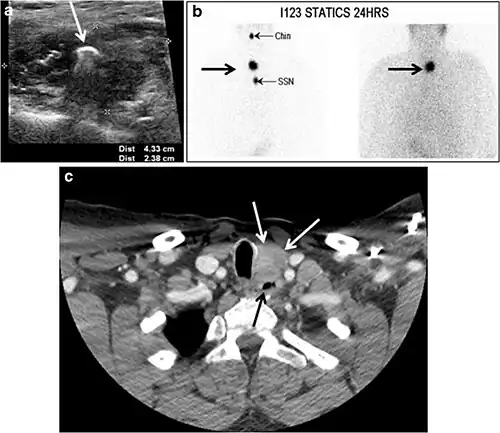

Fig. 4. A 45-year-old male patient presented with anterior mediastinal metastatic PTC lesions and occult primary on imaging. Histopathology examination of the resected thyroid gland revealed micro-foci of PTC; the largest, in the isthmus, measured 4 mm. a transverse greyscale ultrasound of the thyroid demonstrates homogeneous gland with normal echogenicity and size. No focal lesion or micro-calcifications. b Non-enhanced CT scan obtained as part of PET/CT examination shows a heterogeneous, large, relatively dense anterior mediastinal mass (white arrow) with peripheral calcification (arrowheads). Thyroid gland has normal CT appearance with no abnormal FDG uptake (not shown).[1] -